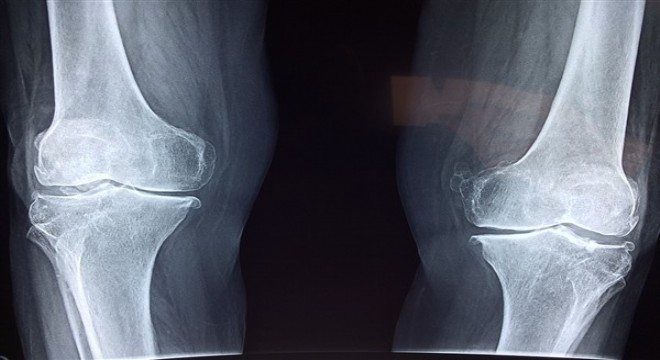

Diz, omuz veya kalçada yaşanan kıkırdak hasarları şiddetli eklem ağrılarına yol açabiliyor.

Diz, omuz veya kalçada yaşanan kıkırdak hasarları şiddetli eklem ağrılarına yol açabiliyor. Son yıllarda öne çıkan kök hücre tedavisi ise genellikle cerrahi yöntemler için uygun olmayan hastalarda başarılı sonuçlar vererek ağrıları ortadan kaldırıyor ve yaşam kalitesini yükseltiyor. Memorial Ataşehir Hastanesi Ortopedi ve Travmatoloji Bölümü’nden Prof. Dr. Haldun Orhun, kıkırdak hasarlarında uygulanan kök hücre tedavisi hakkında bilgi verdi.